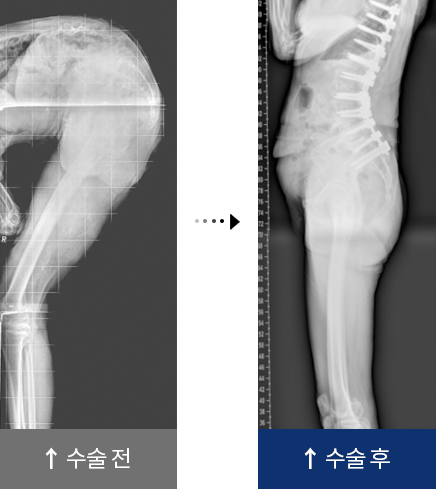

퇴행성 요추 후만증